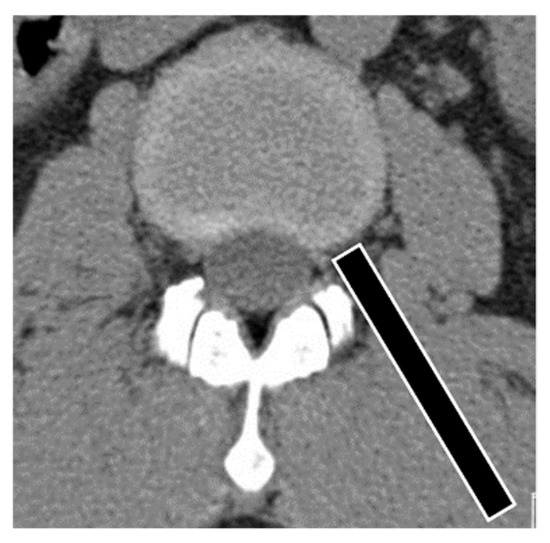

2.4. Surgical Technique

Figure 2. Angle of endoscopic trajectory for the upper lumbar area is steeper than that of the lower lumbar area for the prevention of neurological tissue injury.